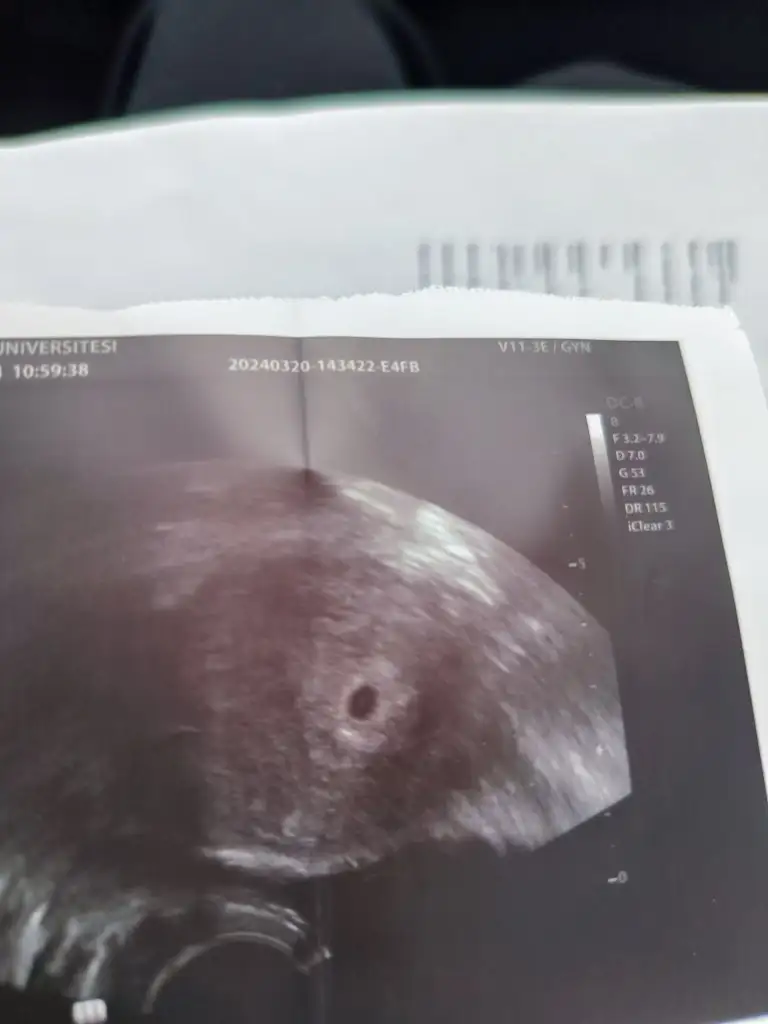

Yaa maşallah canım cok sevindim hayırlı uğurlu olsun sağlıkla hayırlısıyla ilerler inşallahMerhaba kizlar çok şükür keseyi gördük, Dr vajinal ultrasonla baktı, pıhtılaşma ihtimaline karşı oksapar iğne başlıyorum bugün itibariyle. 2 kaybim var inşallah bunu sağlıkla kucağıma alırım.Allahim hepinize sağlıklı gebelik nasip etsin inşallah kızlar, dualarım hep sizlerle. Bu aradamelegim can sen cinsiyet tahmini yapıyordun canım 5 haftalık vajinal ultrason ne dersin

Yaaaa canım benim çok sevindim inşallah sağlıcakla kucağına alırsın. Darısı bizeMerhaba kizlar çok şükür keseyi gördük, Dr vajinal ultrasonla baktı, pıhtılaşma ihtimaline karşı oksapar iğne başlıyorum bugün itibariyle. 2 kaybim var inşallah bunu sağlıkla kucağıma alırım.Allahim hepinize sağlıklı gebelik nasip etsin inşallah kızlar, dualarım hep sizlerle. Bu aradamelegim can sen cinsiyet tahmini yapıyordun canım 5 haftalık vajinal ultrason ne dersin

Gözün aydın canım çok sevindim saglıkla ilerler inşallah. Bu sadece kese galiba içinde benek gözükmesi lazım kuzum cinsiyet tahmini yapmak için konumuna göre yorumlucazMerhaba kizlar çok şükür keseyi gördük, Dr vajinal ultrasonla baktı, pıhtılaşma ihtimaline karşı oksapar iğne başlıyorum bugün itibariyle. 2 kaybim var inşallah bunu sağlıkla kucağıma alırım.Allahim hepinize sağlıklı gebelik nasip etsin inşallah kızlar, dualarım hep sizlerle. Bu aradamelegim can sen cinsiyet tahmini yapıyordun canım 5 haftalık vajinal ultrason ne dersin